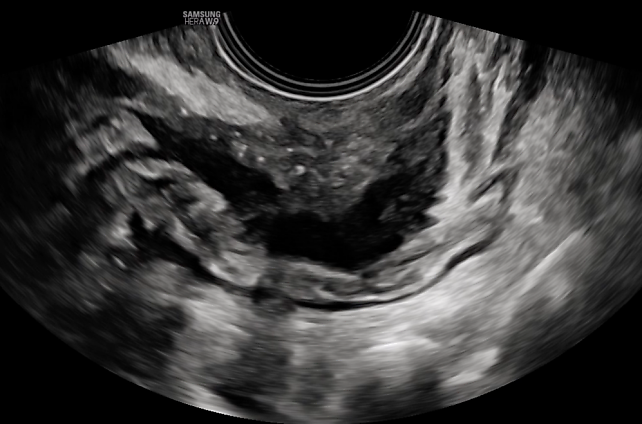

2

Ultrasound image showing an enlarged globular uterus, with diffuse fan-shaped shadowing and an irregular junctional zone. This is indicative of severe diffuse adenomyosis, Type 1–3.

3

Ultrasound image showing asymmetry between the anterior and posterior myometrium and an irregular junctional zone. This is indicative of moderately diffuse adenomyosis, Type 1–2.